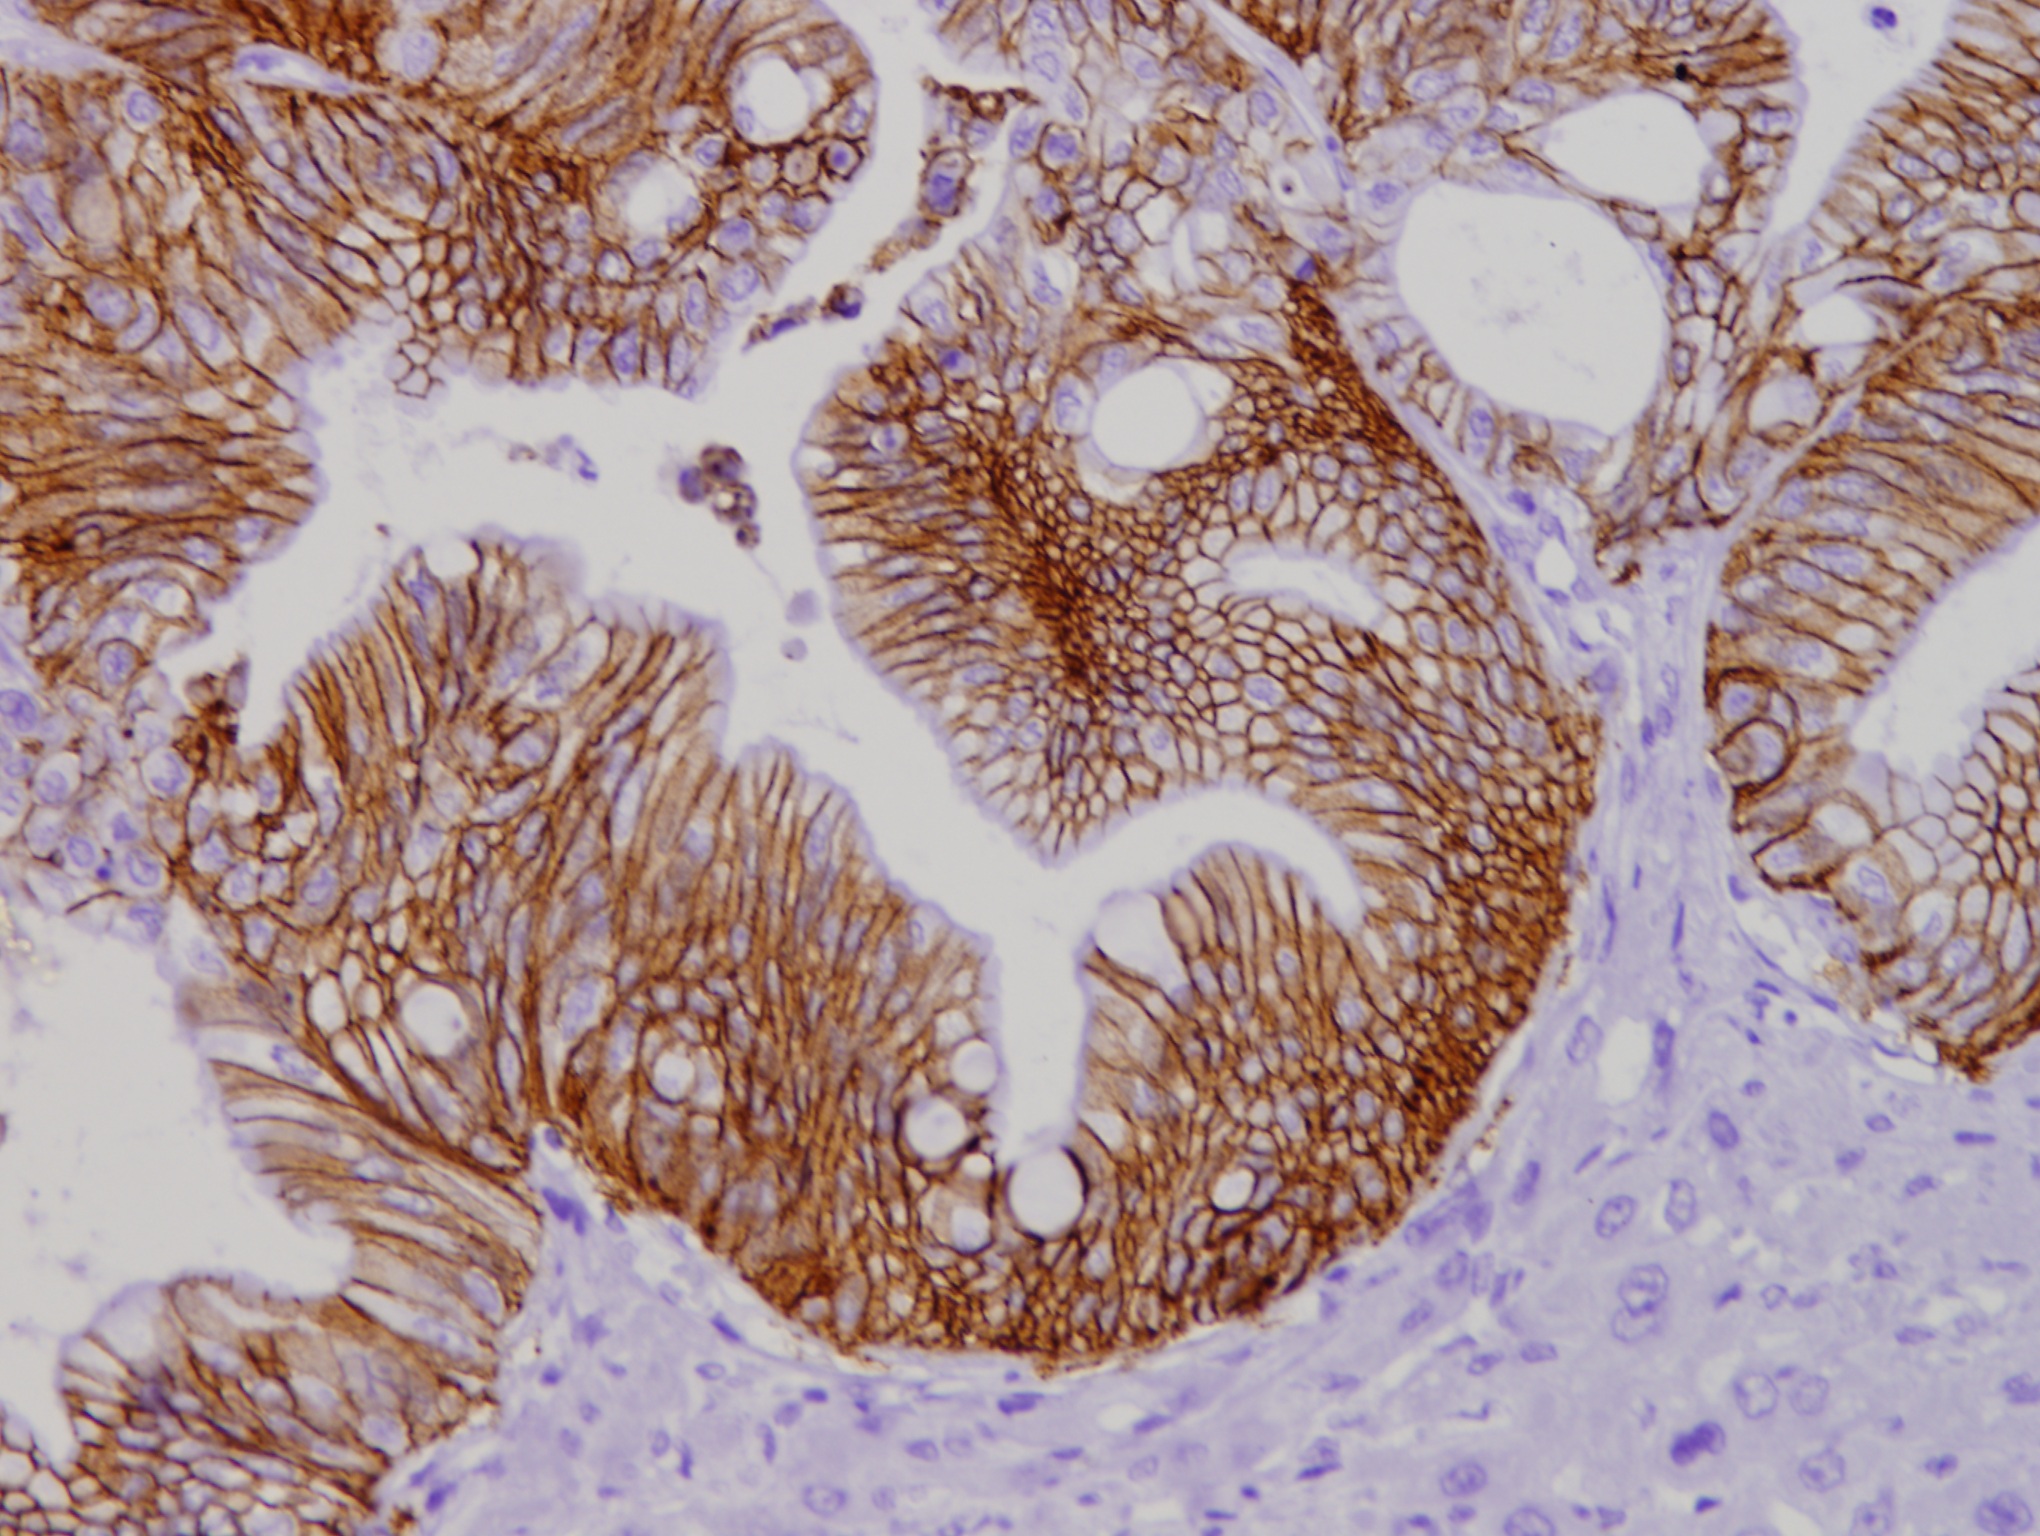

The study was conducted using organoids derived from colorectal cancer patient cells in which the IKKα kinase had been removed. Subsequently, in preclinical mouse models, the researchers demonstrated that "there is a specific subpopulation of tumor cells, characterized by particularly robust cell junctions, that is responsible for generating liver metastases," notes Dr. Espinosa. This cell population was clearly enriched in the absence of IKKα, which explains why tumors deficient in this protein exhibited greater metastatic capacity. Paradoxically, although this protein had previously been described as a tumor promoter in other contexts, the new study reveals that it may also act as a metastasis suppressor in colorectal cancer.

The researchers also showed that inhibiting certain proteins involved in these cell junctions, such as claudin-2, significantly reduces the tumor cells' ability to produce metastases.